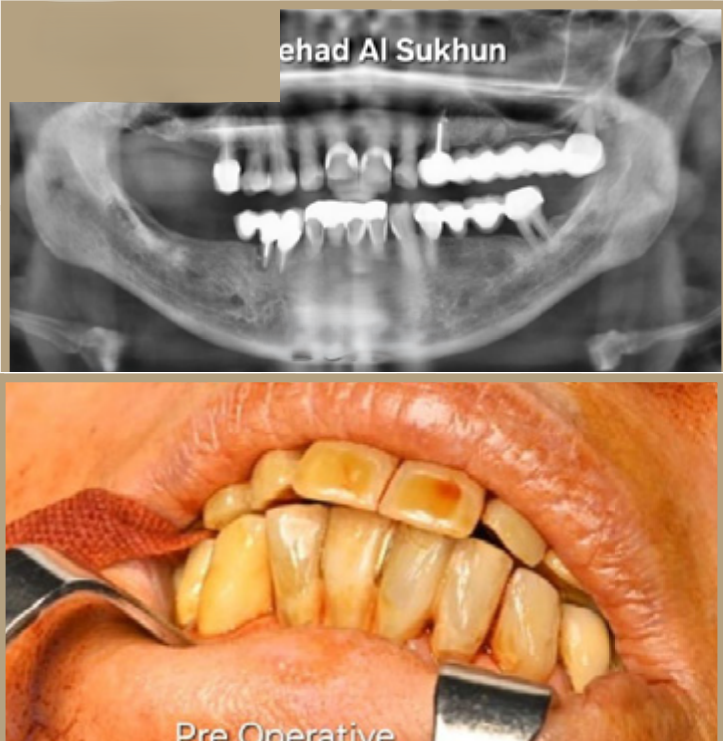

إذا كنت ترغب في الحصول على أسنان ولا تملك ما يكفي من العظام لإجراء علاج الزرع، لم يعد هناك حاجة إلى زراعة العظم من الآن فصاعدا.

تقدم زراعة الأسنان تحت السمحاق ثلاثية الأبعاد (3D subperiosteal implants) حلاً موثوقًا للحصول على أسنانك، خاصة في الحالات التي تكون فيها كمية العظام غير كافية لدعائم الزرع التقليدية.

عوده دون الحاجة إلى الخضوع لعلاج ترقيع عظمي واسع النطاق.

هذه التقنية ثورة في استبدال الأسنان!